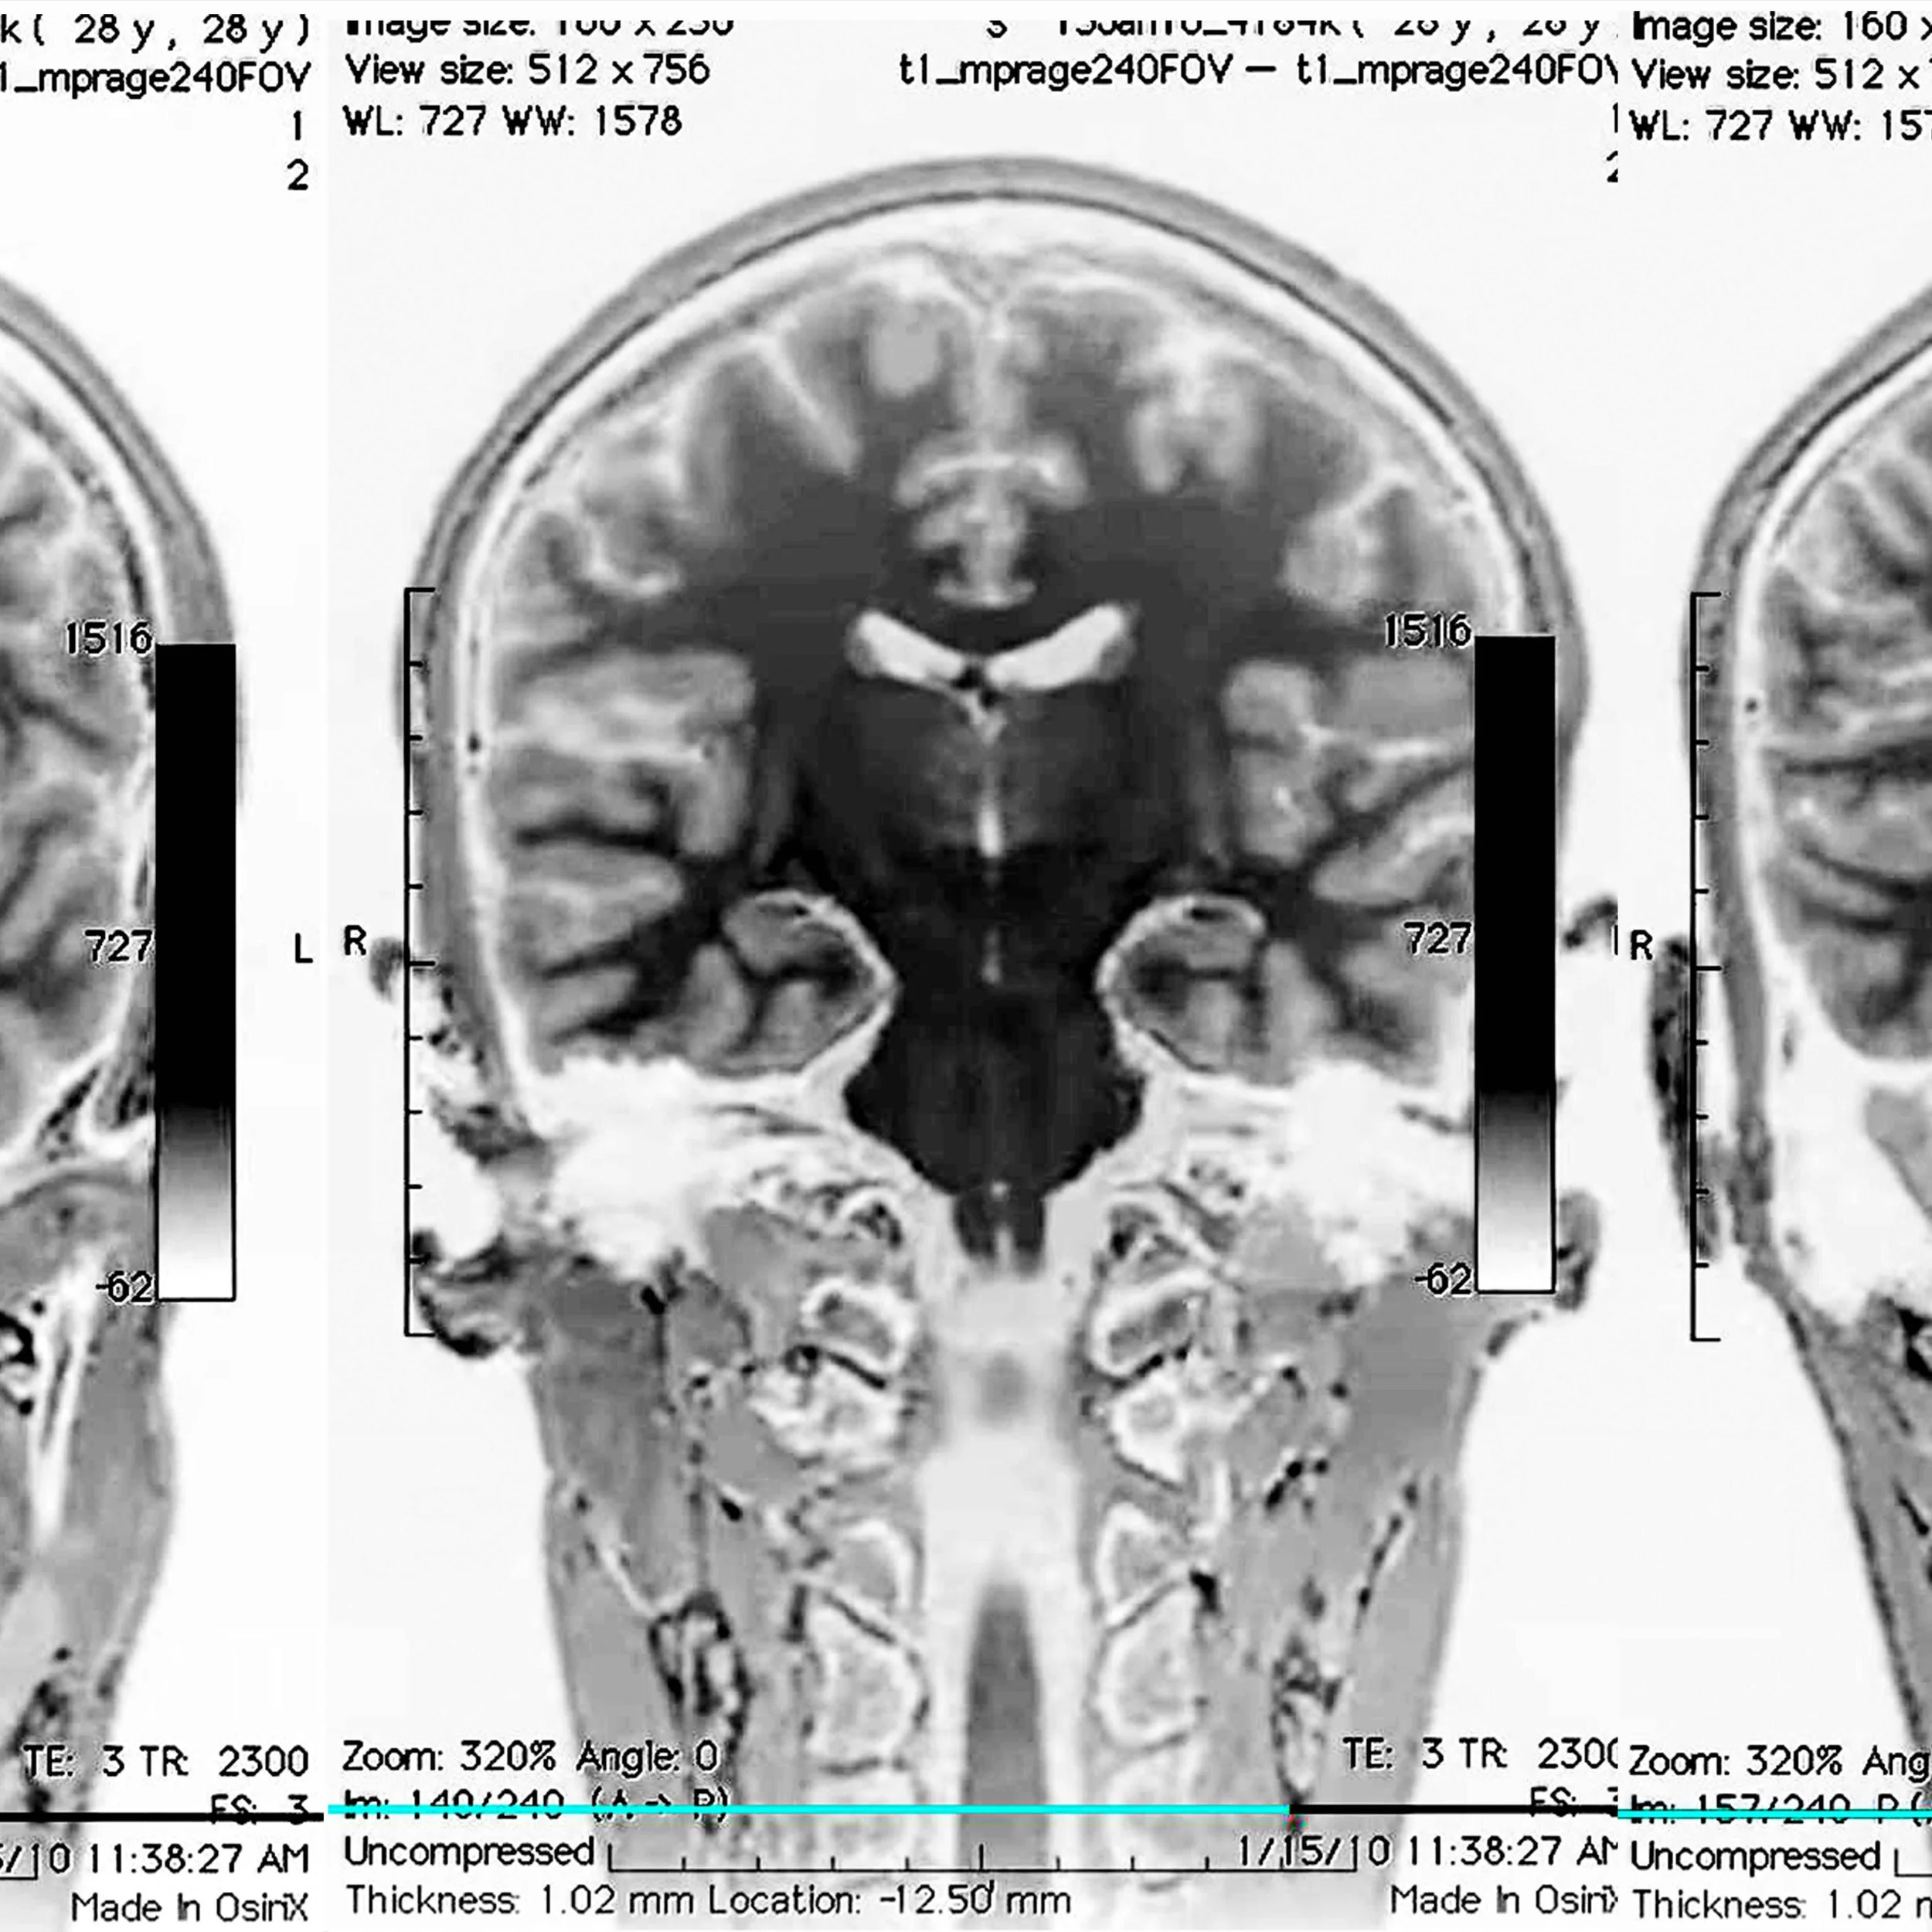

The 6-day program offers students a unique opportunity to experience different aspects of brain research in an authentic laboratory, learning about the tools and discoveries that shape our understanding of the brain. Students will work with real human brain specimens, use microscopes and research-grade lab equipment, practice radiology, and evaluate cognitive functions such as memory, perception, and attention using clinical tools.